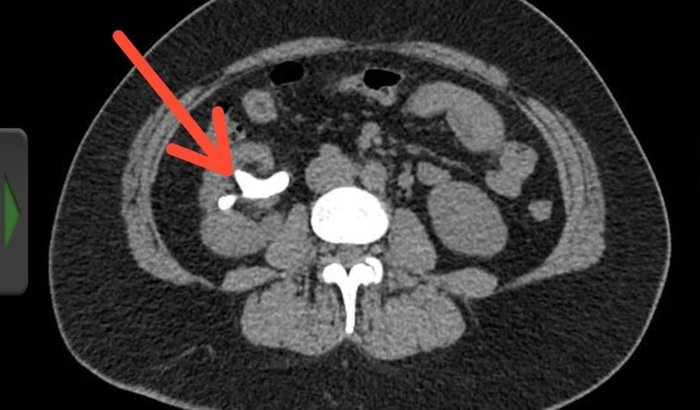

Eu sou a Mayra e criei esta vakinha para ajudar minha mãe, Tatiane, que desde 2018 sofre com um cálculo coraliforme no rim com presença de bactéria. Desde então, ela enfrenta: dores constantes e crises renais que a fizeram perder qualidade de vida; sangramento na urina e infecções urinárias frequentes; perda parcial da função do rim; e o mais preocupante: resistência bacteriana crescente, dificultando os tratamentos com antibióticos. Além disso, ela sofre com a impossibilidade de trabalhar por conta das dores intensas, e com a dificuldade de não conseguir levar minha irmã. que é autista, em todas as suas terapias diante das crises renais. Minha mãe está desde 2018 aguardando na fila do SUS para realizar a cirurgia, mas apesar da gravidade do quadro, hoje, em 2025, ainda não temos nem esperança dela ser chamada pelo SUS para realizar a cirurgia.

Buscamos a opção da vakinha, pois não temos como custear os gastos da cirurgia particular e, segundo os médicos, a única forma eficaz de tratamento é a remoção da pedra, pois ela abriga as bactérias que causam a infecção, podendo evoluir para sepse e morte. Os exames de urocultura já identificaram duas bactérias: Enterococcus faecalis e Klebsiella pneumoniae, ambas resistentes a diversos antibióticos. Segundo o critério de SWALIS, ela se encontra na categoria A1: risco potencial de progressão rápida da doença passível de causar uma disfunção grave, irreversível ou até mesmo óbito.